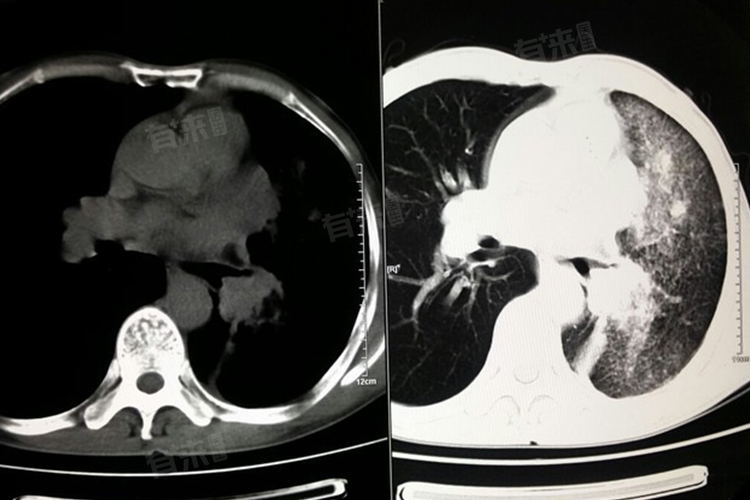

1、X线检查和CT检查:X线检查可以初步显示肿瘤的部位和大致病变范围,还能观察到周围管腔变窄情况及生长方式。CT检查分辨率更高,能发现肺部微小病变,对早期肺癌的检出率较高。